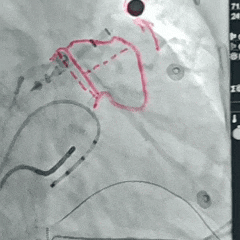

术中DSA造影复测缺损

DSA肝位造影,心耳形态为鸡翅型;

-

DSA下造影开口29.53mm,深度25.35mm;

房间隔穿刺点靠下,从轴向避免心耳上缘的压迫。

封堵器展开后造影

封堵器展开后肝位造影,封堵器完全封堵,无残余分流